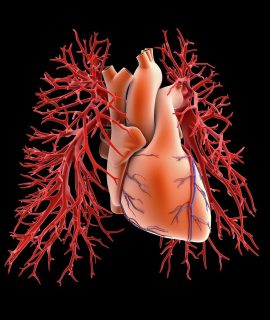

She has brought together a dynamic group of highly skilled professionals, each an expert in their field. Our talented 3D animators combine technical precision with artistic creativity, crafting lifelike, interactive visuals that simplify even the most complex medical concepts. Our production team transforms ideas into captivating cinematic narratives, ensuring each project resonates deeply with its audience. Patient storytellers and communication specialists capture the human essence of healthcare breakthroughs through heartfelt testimonials and insightful KOL interviews that inspire trust and connection.